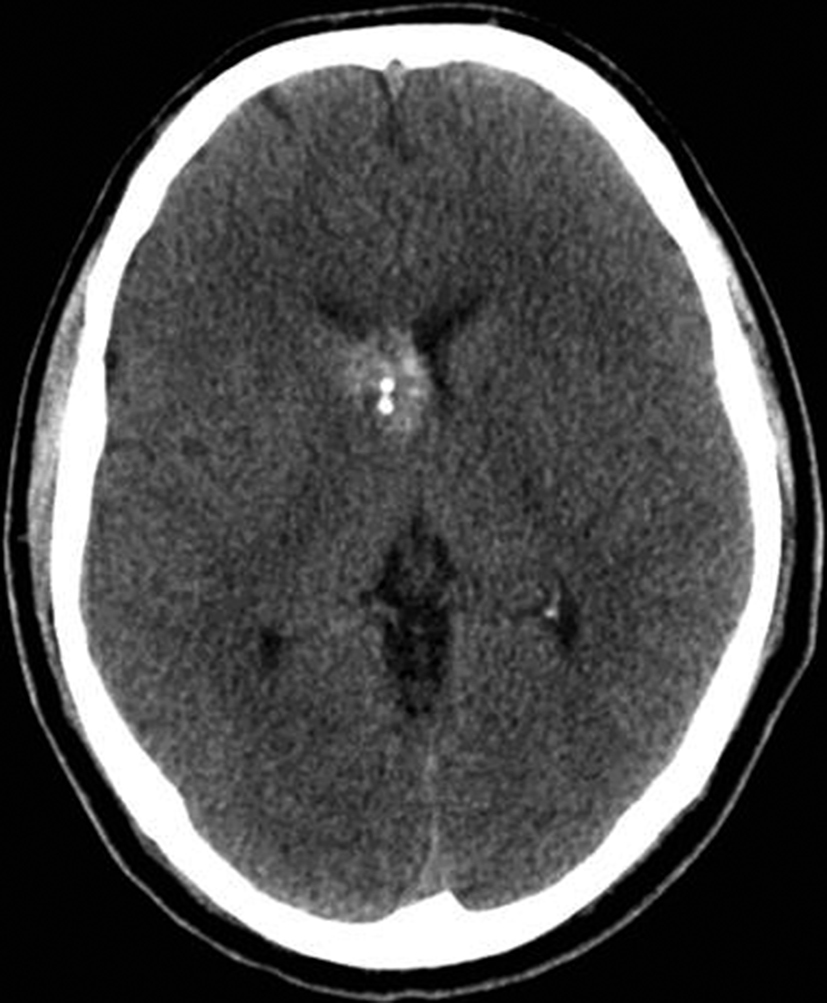

Se presenta el caso clínico de un paciente de sexo masculino, de 36 años de edad, sin antecedentes personales a destacar. Consulta por cefalea holocraneana de larga data, sin déficit neurológico y examen físico normal. Dada la clínica del paciente se realiza una tomografía computada de cráneo sin contraste intravenoso que identifica una lesión bien definida espontáneamente hiperdensa, heterogénea con calcificaciones puntiformes localizada en el asta frontal del ventrículo lateral derecho. No hay edema peri-lesional, efecto de masa ni hidrocefalia (Figura 1- A). Debido a los hallazgos se decide administrar contraste intravenoso, no evidenciándose realce significativo de la lesión (Figura 1- B).

Se efectúa un control imagenológico al año del diagnóstico mediante una TC sin y con contraste (Figura 5 – A y B), donde se evidencia la lesión sin cambios significativos en cuanto a su tamaño y características.

Figura 1

a) TC sin contraste. Lesión

intraventricular hiperdensa,

heterogénea con pequeñas

calcificaciones.

a) TC con contraste. No se

identifica realce significativo

de la lesión.

Figura 5

a y b) Cortes axiales de TC sin y con contraste intravenoso. Control

tomográfico al año

del estudio inicial, no

se observan cambios

significativos de la lesión.

En la TC sin contraste, el cavernoma es una lesión bien

definida e hiperdensa. El aumento de la densidad puede

tener un aspecto punteado, que puede representar calcio,

sangre o una combinación de ambos y el realce tras

la administración de contraste varía de ninguno a muy

intenso (1,3,5).